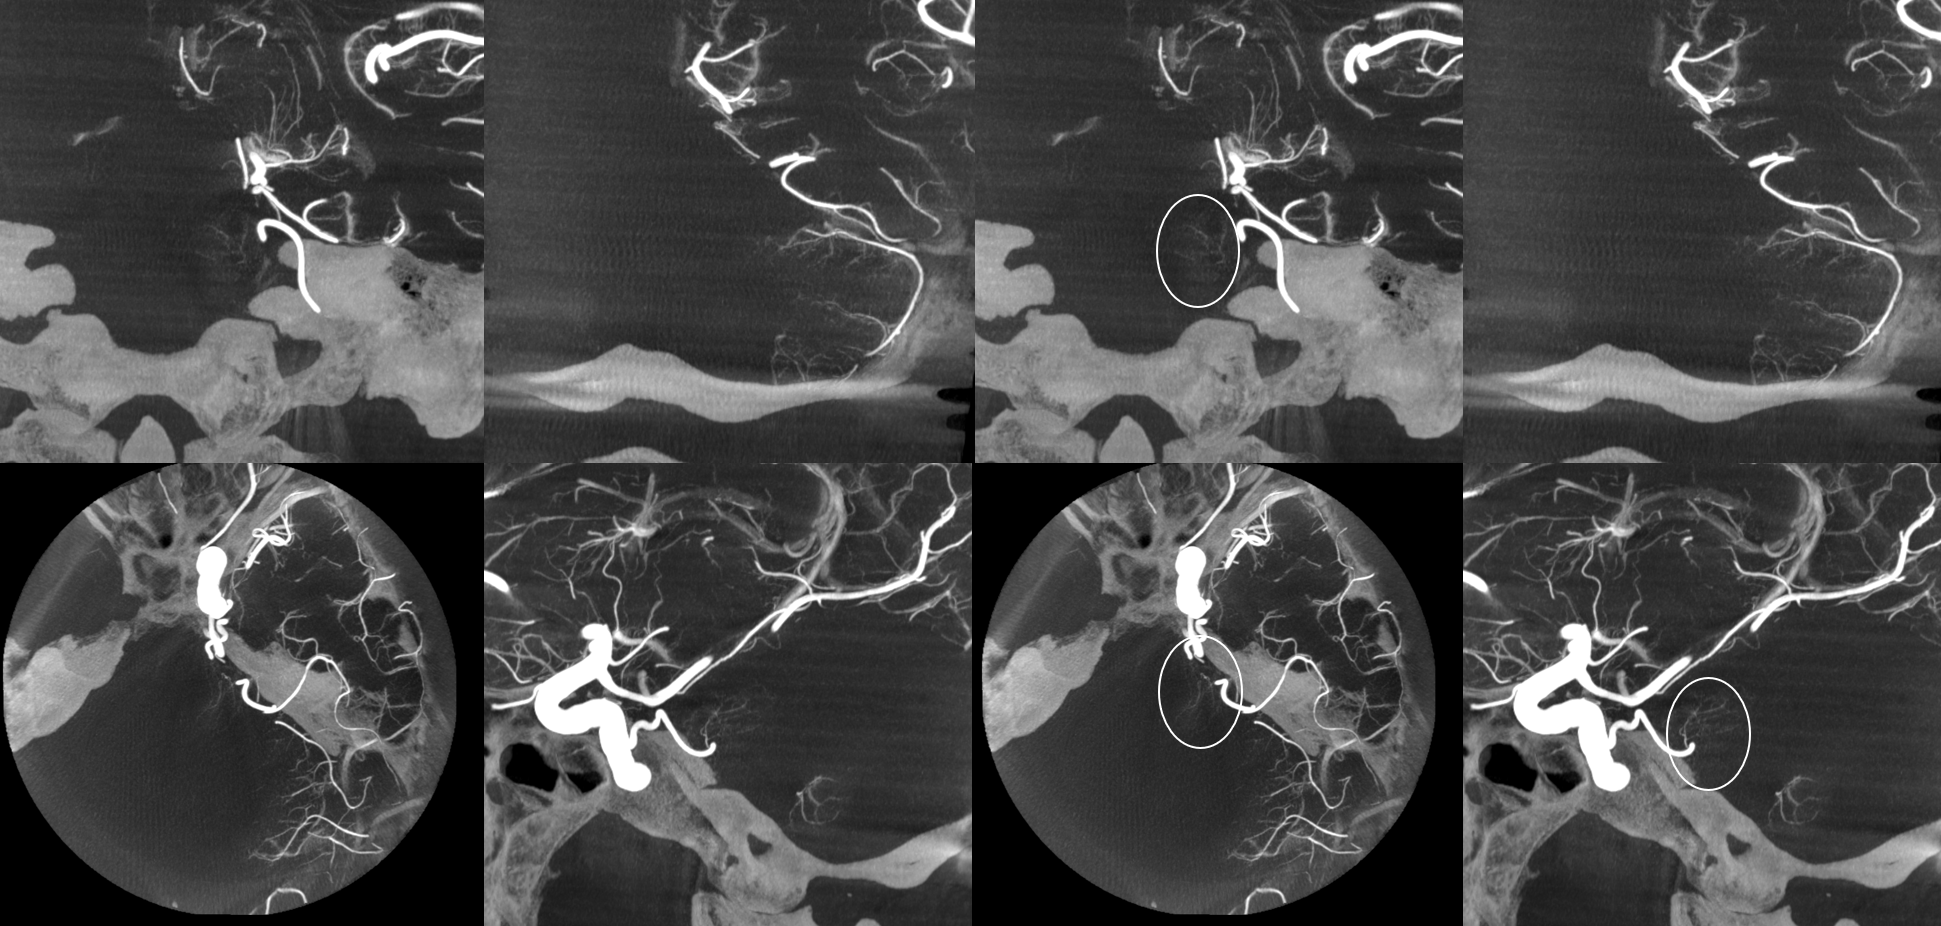

And, in case you really dont believe its the trigeminal artery, check out these co-registration images of angio (axial MIP reconstructions of rotational angio) and finally with superimposed tractography of the Vth nerve! Images courtesy Dr. Nader Delavari

Superimposed MRI and angio axials (our trigeminal artery is shown bi arrow)

Now with tractography of CN V